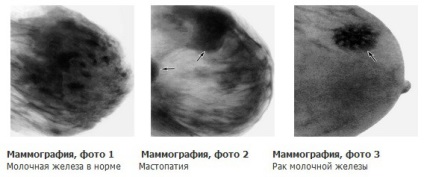

Mammográfia feltárja jóindulatú és rosszindulatú daganatok korai szakaszaiban. Íme négy alapvető változata, amely már látható értelmezésekor mammográfia:

- Fibroadenóma. Ártalmatlan jóindulatú - a tőle telhető legjobban találni egy orvost. Ez általában sebészileg eltávolítják, majd a pácienst küldött további vizsgálatra. Gyakran diagnosztizált fiatal nők.

- Ciszták. A mammogram megkülönböztethetetlen tumorok igényel további diagnosztikai (általában, ez a US - ultrahang hullámok áthaladnak a ciszta, és amelyeket a tumor). A mérete és szerkezete (közelítő) után tüntettük dekódolási eredmények. Leggyakrabban ez egy üreg belsejében történő és rendkívül vékony, rugalmas falak. Diagnosztizált idősebb nők gyakrabban - fokozták 30 éves mérföldkő.

- Mell tejmirigyek. Arra utal, hogy jóindulatú kórképek. Jelenleg több mint 50 féle formáció, de világos azok okait, az orvosok nem nevezhető. Felvett ritka esetekben, amikor a mell az a jel, feltörekvő mellrák. Nincs további tüneteket, sokan közülük egyáltalán egybeesik a megszokott élettani megnyilvánulásai menstruáció. Diagnosztizált betegeknél minden korban.

- Más szervezetek (például a - meszesedés). Sokan közülük lehetnek jóindulatú vagy rosszindulatú. Például, kis és több fürt kalcium sók lehetnek prekurzorok rák, míg egy oktatási marad jóindulatú. Rész nincs kimutatható tumor a vizsgálat során (kivéve az utolsó szakaszában a betegség, amelynél terápia hatástalan, és még a műtét), hogy a mammográfia - az egyetlen módja annak, hogy a betegség észlelése, mielőtt elkezd lassulni megöli a beteget. Sokkal gyakoribb az idősebb nők.